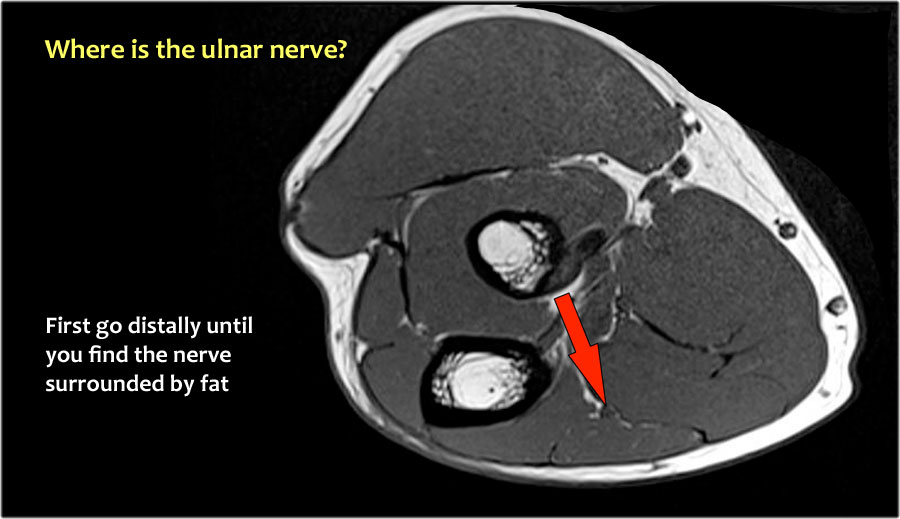

Vì vậy, khi chúng ta quay lại hình ảnh, bạn sẽ nhận thấy rằng có thể khó tìm thấy dây thần kinh.

Bất kỳ cấu trúc dưới da nào trong số này đều có thể là dây thần kinh đã được chuyển vị.

Một cách để thực hiện là đi theo các cấu trúc về phía xa cho đến khi tìm thấy dây thần kinh trụ ở phía xa tại vị trí bình thường của nó ở vùng cẳng tay gần được bao quanh bởi mô mỡ.

Sau đó khi bạn theo dõi nó về phía gần, bạn sẽ nhận thấy rằng đây là một trường hợp chuyển vị dưới da.

Trong trường hợp này, có viêm dây thần kinh.

Có sự phì đại của dây thần kinh.

Trên hình ảnh T2W có tín hiệu cao.

Dấu hiệu khác là sự phì đại không đồng đều của các bó sợi thần kinh, được thấy trên hình ảnh mặt phẳng đứng dọc (mũi tên).